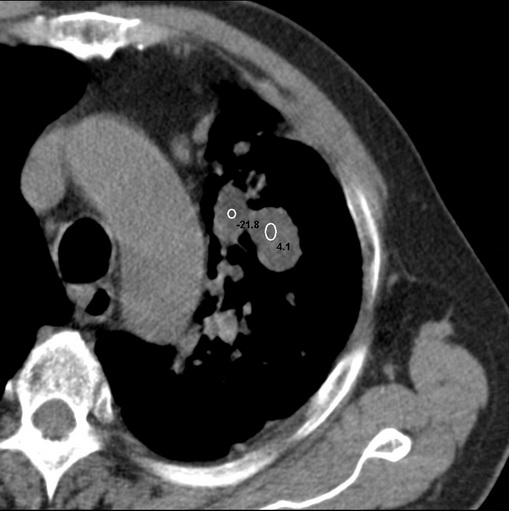

标题: CT25434:胸部CT增强扫描

男性患者 81岁 咳嗽 咳痰 咯血

肿块贴近左肺门,包绕左上肺动脉,形态不规则。肿块增强扫描中度强化。纵膈内主动脉弓左旁间隙、气管隆突前、下间隙见多枚淋巴结影。综上考虑左侧中央型肺癌可能性大。图片没有完整上传,尤其是左肺上叶支气管分支层面没有上传,因此不好判断是叶支气管中断还是段支气管中断。另外,下图红色部分所示是“黏液支气管征”吗?